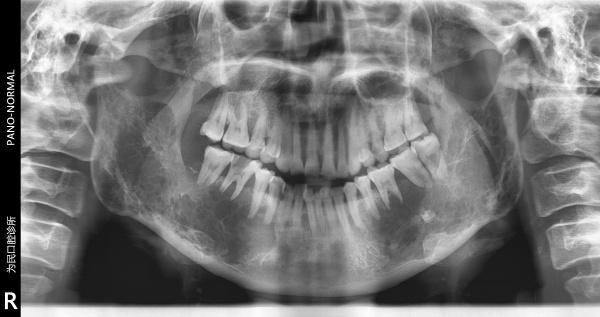

恶性造釉细胞瘤??

下颌骨2

不过从片子没看出有锯齿样吸收

不常见的病例啊 范围挺大